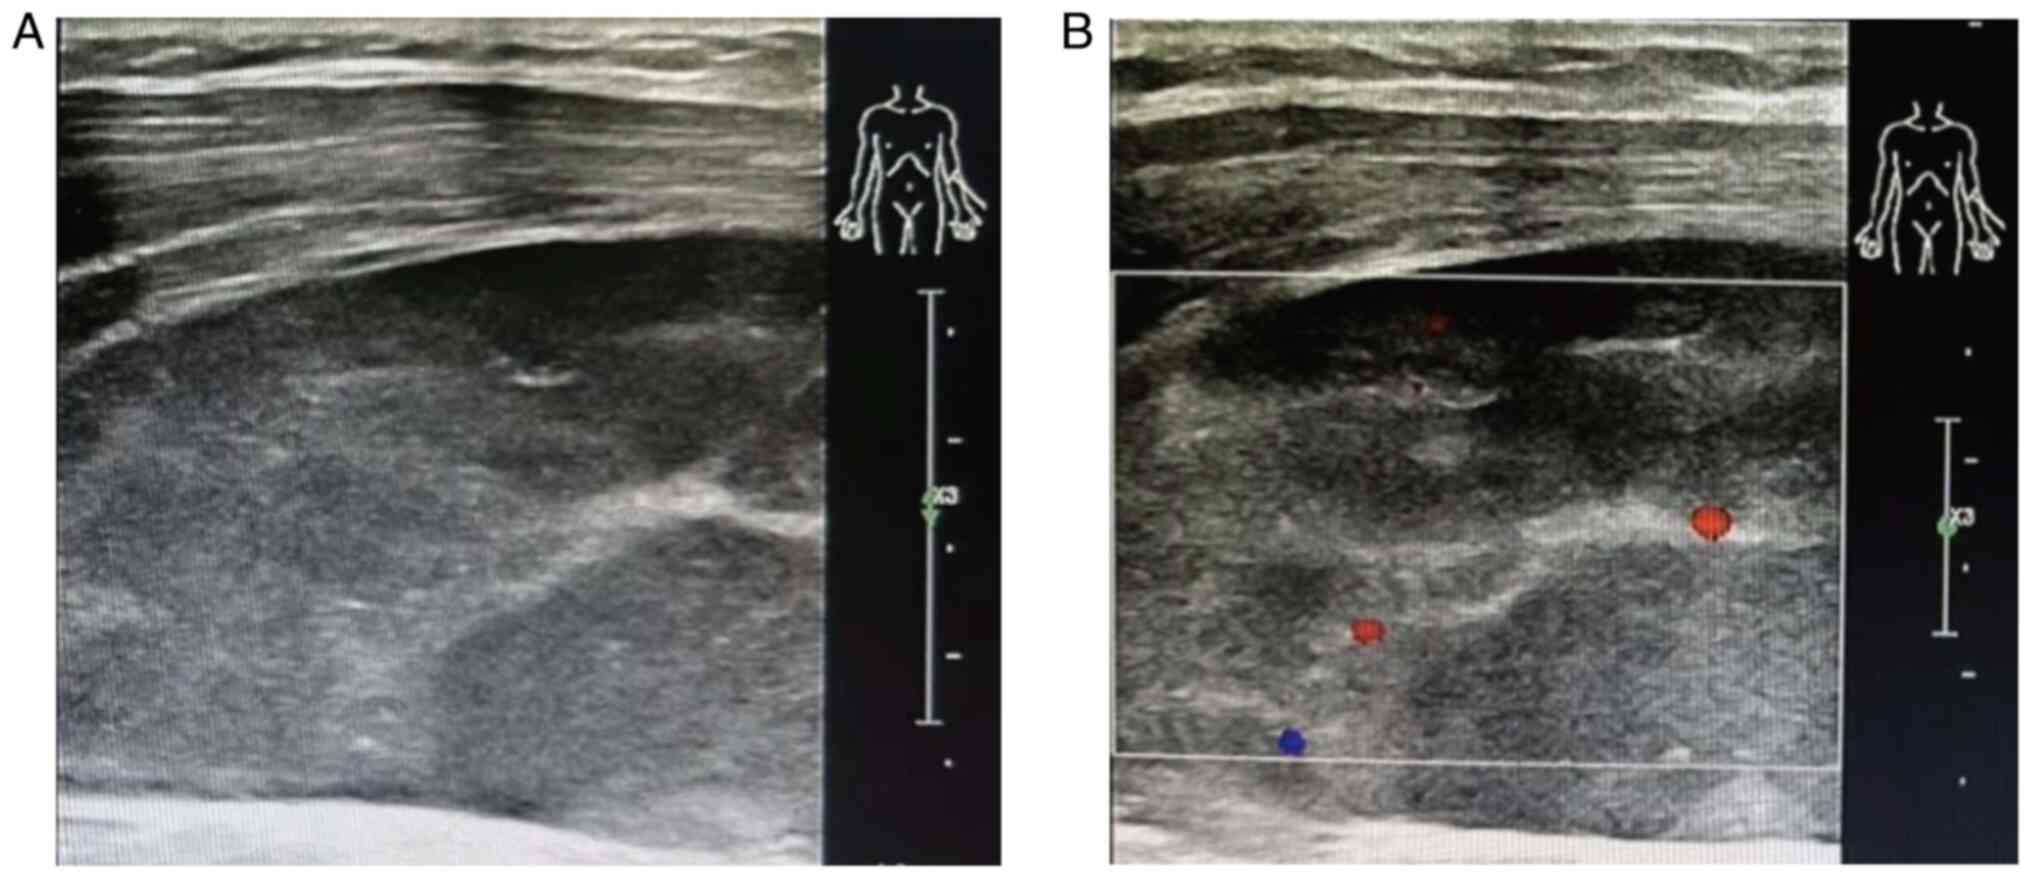

Primary gingival diffuse large B‑cell lymphoma (DLBCL) with muscle invasion is rare and accounts for ~0.5% of all reported cases of extranodal lymphoma. The present study describes the case of a 49‑year‑old man that initially presented at Yingshan County People's Hospital (Nanchong, China) in August 2017 with a chief complaint of tenderness and swelling of the jaw. Computed tomography revealed a mass in the gingiva, and enlarged lymph nodes in the cervical, mediastinal and gastro‑hepatic ligaments. Histological examination indicated the gingival mass was a DLBCL, which was positive for CD20, BCL‑6, BCL‑2, C‑MYC and MUM1. The patient received three lines of anti‑neoplastic therapy (R‑CHOP, R‑CHOEP and SYHX1903) and achieved stable disease for 6 years. Subsequently, the patient experienced trauma in the left forearm due to a car accident and the subsequent color Doppler imaging led to a diagnosis of muscular hematoma; however, magnetic resonance imaging and biopsy of the forearm muscle confirmed DLBCL invasion. Due to the patient suffering from heart failure after the third line of the previous chemotherapy, palliative radiotherapy was administered to the left forearm, and the patient achieved a partial response. In conclusion, primary gingival DLBCL with muscle invasion is rare and easily misdiagnosed, and individualized treatment should be considered for these complex cases.

Figure 4